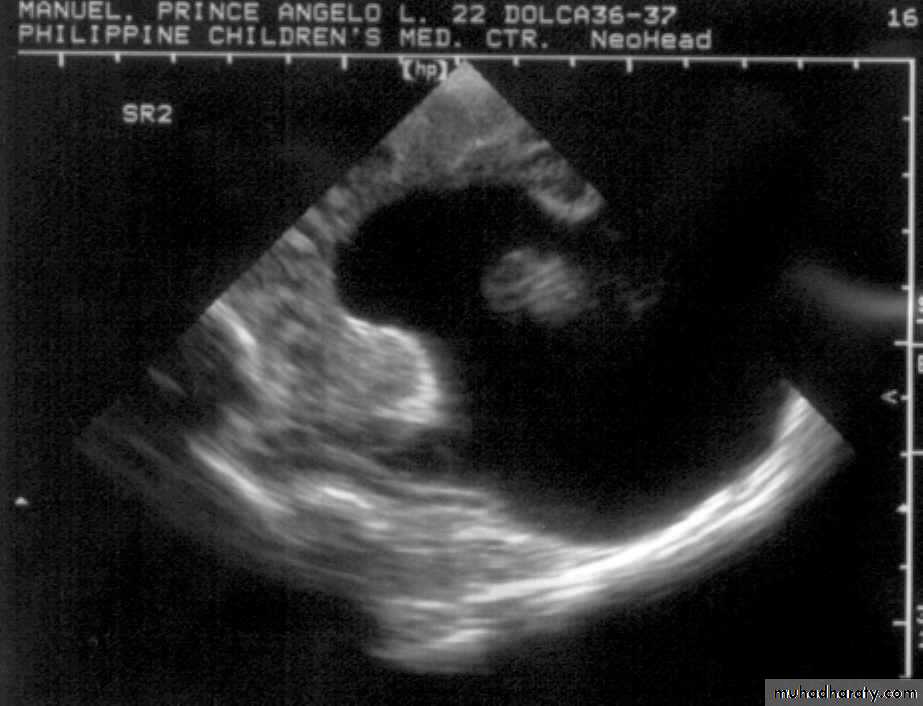

A.M., 2 months old

was noted to be microcephalic w/ szPorencephalic Cyst

SchizencephalyAbsent Septum Pellucidum

Dysgenetic Corpus Callosum

Aqueductal Stenosis